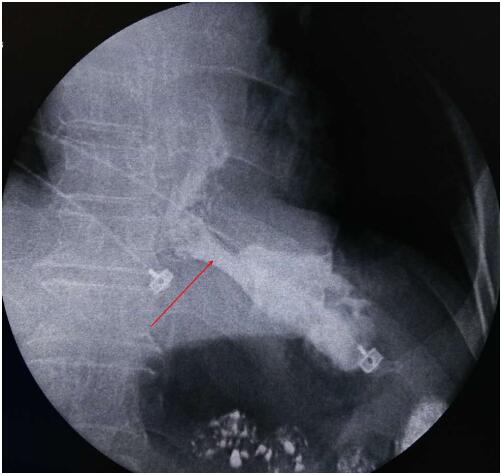

栓塞完成后再次造影

提示肿瘤供血动脉分支明显减少,大部血流中断

此例手术的成功开展,标志着我院放射科介入微创手术治疗达到了一个新的水平。造影剂顺利通过支架进入胃内